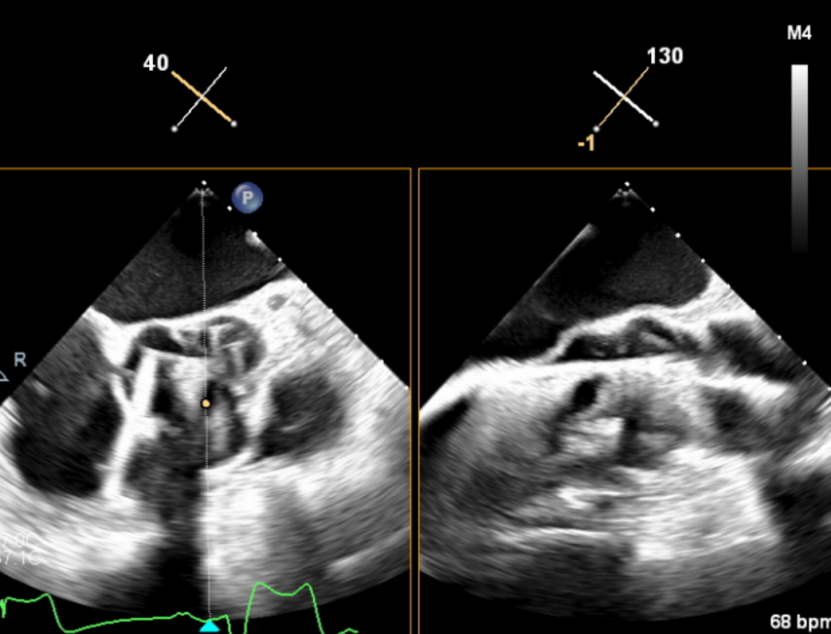

输送器顺利跨瓣,释放外鞘管,开始定位释放,超声评估可见定位件入窦可,后释放内鞘管,打开瓣架,瓣叶活动良好,无瓣周反流,综合考虑瓣膜稳定良好,脱钩释放。

(瓣膜展开)

(瓣膜脱钩)

脱钩后输送器回收,瓣膜无位移及形变,确认瓣膜完全脱钩,回撤输送系统,超声再次评估,瓣膜位置及形态良好,无瓣周漏,峰值流速1.18m/s,平均压3mmHg,患者未诉不适,入路缝合后返回病房。